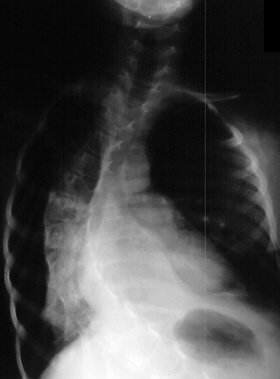

Radiographic evaluation at age of 3 showed mild scoliosis

and bilateral dislocated hips.

Age 6 scoliosis progressed to 78 degrees

and PSF with the unit rod

was performed.